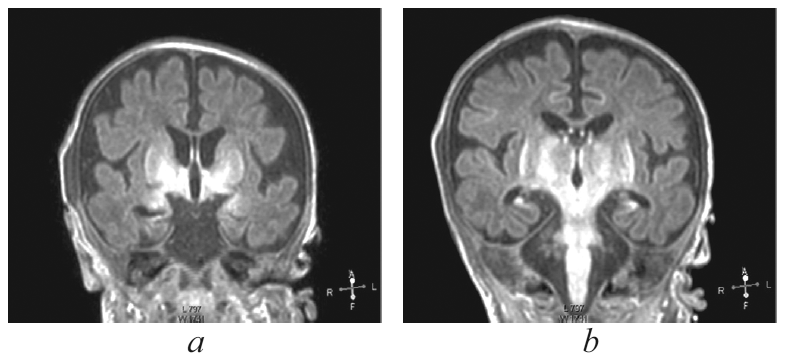

Краниальную сонографию выполняли в динамике. При выполнении КСГ в последующие месяцы отмечалось нарастание атрофических изменений головного мозга — расширение субарахноидальных пространств (до 15 мм), истончение кортикальной пластины, расширение пространств между бороздами и извилинами, расширение боковых (передних и центральных отделов) и третьего желудочков мозга (рис. 3).

Рис. 3. Краниальная сонография пациента. Фронтальный скан в В-режиме / Fig. 3. Cranial ultrasound. Frontal scanner B-image

Визуализируется смешанная гидроцефалия по атрофическому типу (расширение субарахноидальных пространств, межполушарной щели, передних отделов боковых желудочков), истончение корковой пластины, расширение межбороздного пространства.